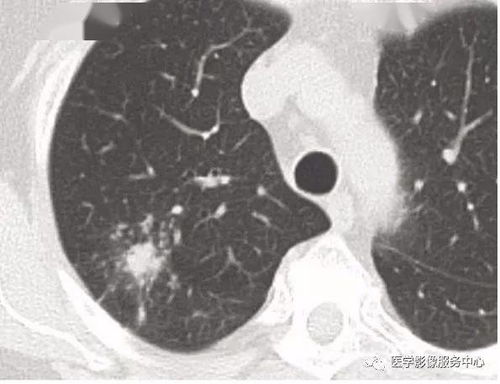

4、定期胸部X線攝片,了解肺膨脹和胸膜腔積液情況。